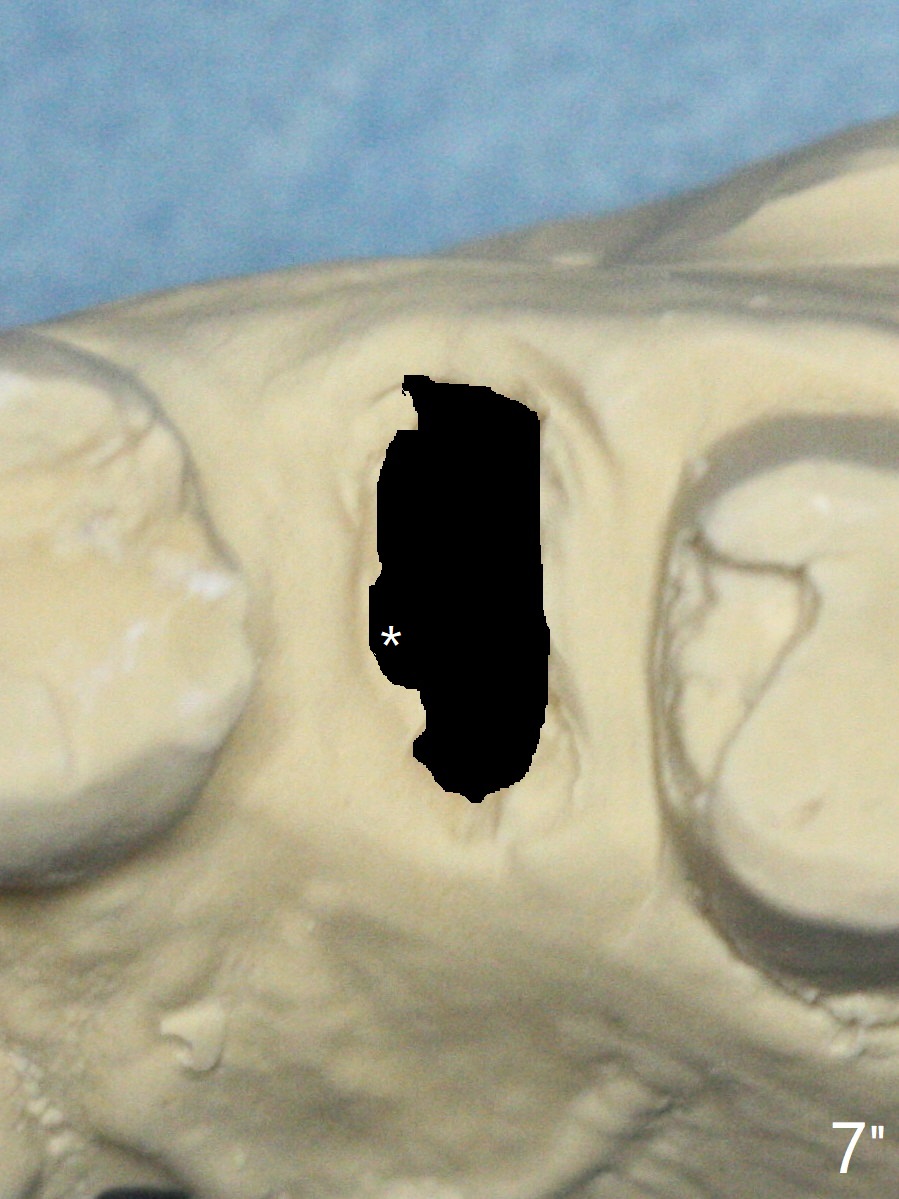

After mesial sheath preparation, insert a guide to finish osteotomy and 4x9 mm dummy implant (Fig.7' green).  Remove the guide to check the relationship between the implant and the sheath.  If needed, remove the middle of the sheath (Fig.7" *).